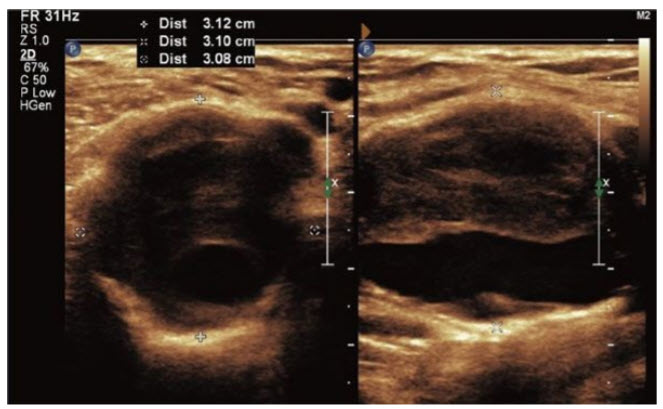

A 65-year-old man presents for a routine physical examination. During the interview he complains about swelling behind his right knee. You order an ultrasound of the area (findings illustrated in figure below).

After finding the results illustrated in Figure above you refer the patient for ultrasound of the abdomen and contralateral popliteal artery. No additional abnormalities are discovered. What is the next appropriate step in his management?

Refer for repair of the aneurysm. Popliteal artery aneurysms measuring greater than 2.5 cm are at risk for thrombosis, embolism, or rupture and therefore should be repaired. Popliteal artery aneurysms measuring less than 2.5 cm are imaged at regular intervals.

What is the most common complication of untreated, symptomatic popliteal artery aneurysms measuring more than 2.5 cm in greatest dimension?

Thromboembolism. Popliteal artery aneurysms most commonly cause thromboembolism that can lead to popliteal artery occlusion or painful distal embolic lesions. Rupture of popliteal artery aneurysms occurs infrequently.